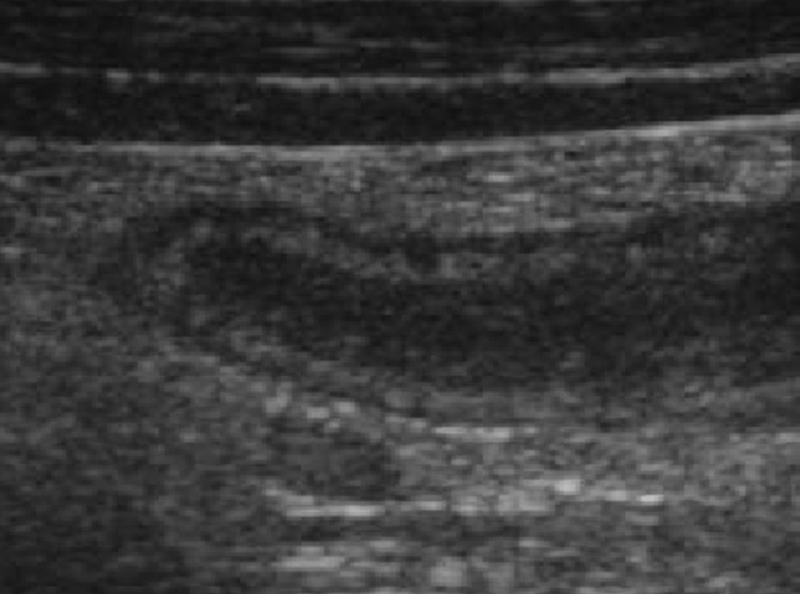

Khi ruột thừa bị viêm trên siêu âm sẽ ghi nhận hình ảnh cấu trúc hình ống, chứa đầy dịch, không đè ép được, thành ruột dày và có đường kính lớn hơn 6 - 7 mm. Khi dùng đầu dò đè lên phần quai ruột cố định chính là ruột thừa viêm, đây là điểm để phân biệt với các quai ruột bình thường sẽ di động.

Thành ruột thừa dày không đồng đều, giảm hồi âm, mất cấu trúc lớp, hoặc cũng có thể thành ruột thừa mỏng, chứa đầy dịch mủ trong lòng ruột thừa. Siêu âm Doppler cho thấy cho thấy không có sự hiện diện của tín hiệu Doppler tức là đã qua giai đoạn sung huyết của thành ruột thừa.